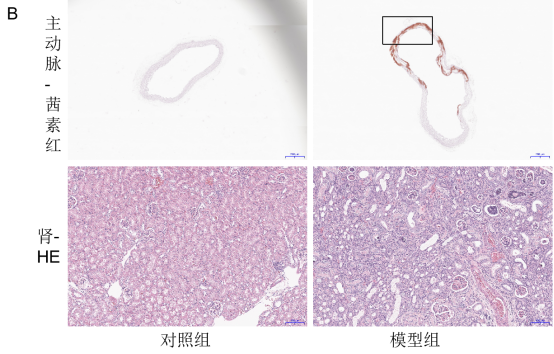

与对照组相比,模型组肾功能指标肌酐(CREA)、尿素氮(UREA)显著升高(P<0.05),肾组织病变明显,主动脉钙化严重(如图 8 所示),充分证明模型构建的有效性。

image.png

图8